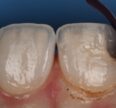

December 4, 2023 Triangular no more. Black triangle minimization completed on #8 and 9 with the Varistrips from Garrison and a single shade of A2 G-aenial A’Chord from GC #GCGaenial #GarrisonDentalSolutions Previous Post Next Post